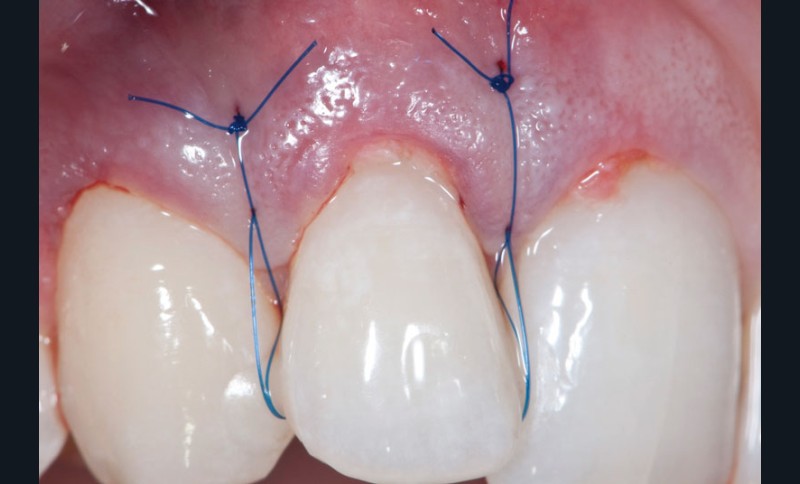

Le concept de microchirurgie a montré un intérêt croissant ces dernières années. Il permet au clinicien de réaliser des interventions chirurgicales très précises et atraumatiques avec des instruments plus petits et des sutures plus fines. Mais, y a-t-il des bénéfices cliniques mesurables ? Les principes de microchirurgie procurent-ils de réels avantages s’ils sont comparés aux concepts conventionnels de chirurgie parodontale ? La conférence du Docteur Zuhr répondra à ces questions et présentera une synthèse des innovations et des évidences scientifiques dans ce domaine.

Jeudi 7 mai : « Appliquer les principes de microchirurgie en parodontologie et en implantologie », conférence du Dr Otto Zuhr

Jeudi 7 mai : « Appliquer les principes de microchirurgie en parodontologie et en implantologie », conférence du Dr Otto Zuhr